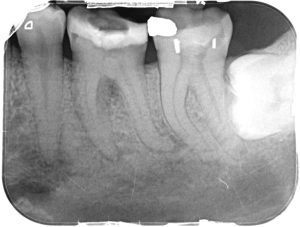

Clinical Cases